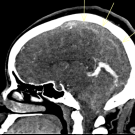

Linda Sherine Alfred, MD; Jenson Ma, MD; Khalid Khumage, MD; Andrew Wilner, MD

A 22-year-old G1P1 with a BMI of 38 and no significant past medical history presented with severe frontal headache 2 days after an uncomplicated vaginal delivery with epidural anesthesia.